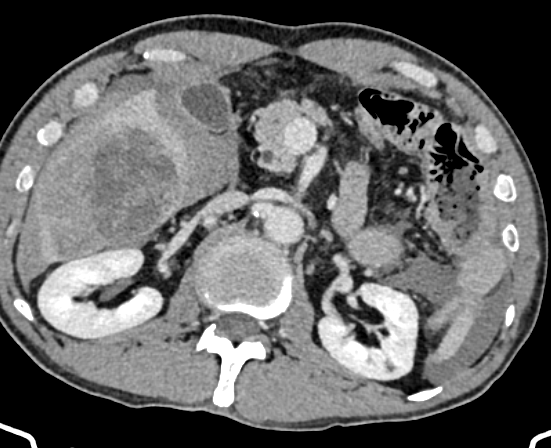

肝癌专病中心MDT于2025年9月正式启动,运行半年来严格落实常态化诊疗机制,成效显著。中心坚持每周2次规范化多学科讨论,打破科室诊疗壁垒,汇聚肝胆、消化、肿瘤、影像、病理、肝病等多学科精锐力量,聚焦各类肝癌的精准诊疗需求。截至目前,已为40余例肝恶性肿瘤患者开展MDT联合诊疗,量身定制手术切除、介入治疗、靶免联合等个性化诊疗方案;2025年肝胆诊疗中心完成100余例肝脏手术,涵盖高难度精准肝切除、腹腔镜及机器人肝切除、5G远程机器人手术,以硬核技术提升诊疗效果,赢得患者及家属广泛认可。